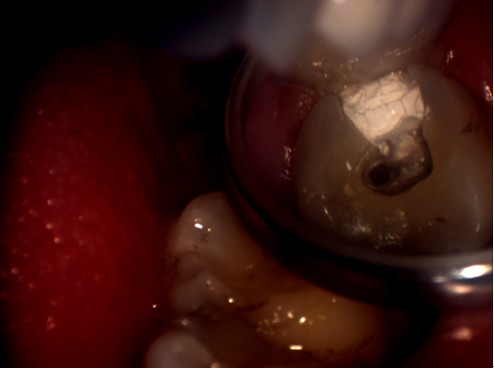

明美工程師在剛開始接觸牙科專用顯微鏡時,對這臺牙科專用顯微鏡有點陌生。牙科專用顯微鏡與其他的顯微鏡有點不同,1米多高的機身,沒有粗微調(diào),調(diào)焦只能通過手動上下移動來實行。在安裝過程中遇到了很多技術(shù)上的難題,如顯微鏡的接口問題,這款顯微鏡的C接口并不是標(biāo)準(zhǔn)的C型接口,有點偏小。經(jīng)過我們工程師專業(yè)的技術(shù)經(jīng)驗及反復(fù)試驗,發(fā)現(xiàn)在它原有的接口的基礎(chǔ)上再接上準(zhǔn)的C型接口,即接兩個C接口就能把顯微鏡相機安接裝上去。但是安裝上去并不能完解決此問題,還有成像方面的問題,由于它原有的C接口不是標(biāo)準(zhǔn)的C口,在實拍的時候,可以達到同步的效果,而且靜態(tài)拍攝圖片效果不錯,但在實際口腔內(nèi)拍攝的時候圖像太暗,若只通過軟件調(diào)節(jié)后,亮度達到了,但是有點反光,通過和技術(shù)人員溝通后,發(fā)現(xiàn)那臺顯微鏡用的是一個普通的照明燈,亮度不可調(diào),通過幾番周折后,通過調(diào)試后亮度問題終于解決。明美工程師在順利安裝完成了,楊主任對此效果表示滿意,亦對明美工程師的專業(yè)技術(shù)能力給予肯定。以下為顯微鏡相機實拍圖片:

顯微圖片

牙科顯微圖片